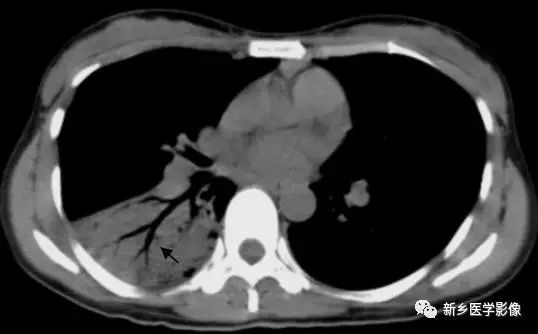

右肺下叶实变CT图:显示空气支气管征(↑)